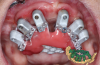

(12.) Intraoral retracted view and scanning software view, respectively, of elongated scan bodies designed to reduce the space between dental implants. The unique shapes of these scan bodies prevent the scanner software from confusing them with one another.

Figure 12

(13.) Intraoral retracted view and scanning software view, respectively, of elongated scan bodies designed to reduce the space between dental implants. The unique shapes of these scan bodies prevent the scanner software from confusing them with one another.

Figure 13

Another approach to tackle intraoral scan stitching issues using traditional multi-unit abutments involves using elongated scan bodies, some of which have unique individual shapes, to minimize the gaps between implants and permit continuous intraoral scanning without interruptions (eg, ArchBridge, ROE Dental Laboratory; Nexus iOS, Keystone Dental Group; Scan Ladder Indirect, ScanLadder; Radar, PartMaker; EZ Ref, Evolve Dentistry) (Figure 12 and Figure 13). The use of distinct scan body shapes prevents the scanner acquisition software from duplicating, overlapping, or confusingly scanning the same object. These unique shapes facilitate simplified surface scanning of the scan bodies, which is particularly useful in immediate surgical cases where scanning is challenging due to a bloody field. Furthermore, importing uniquely shaped scan bodies into acquisition software programs with AI technology can enable scan body matching. After being captured, these scan bodies can be point-matched and aligned to the tissue scans in CAD software.